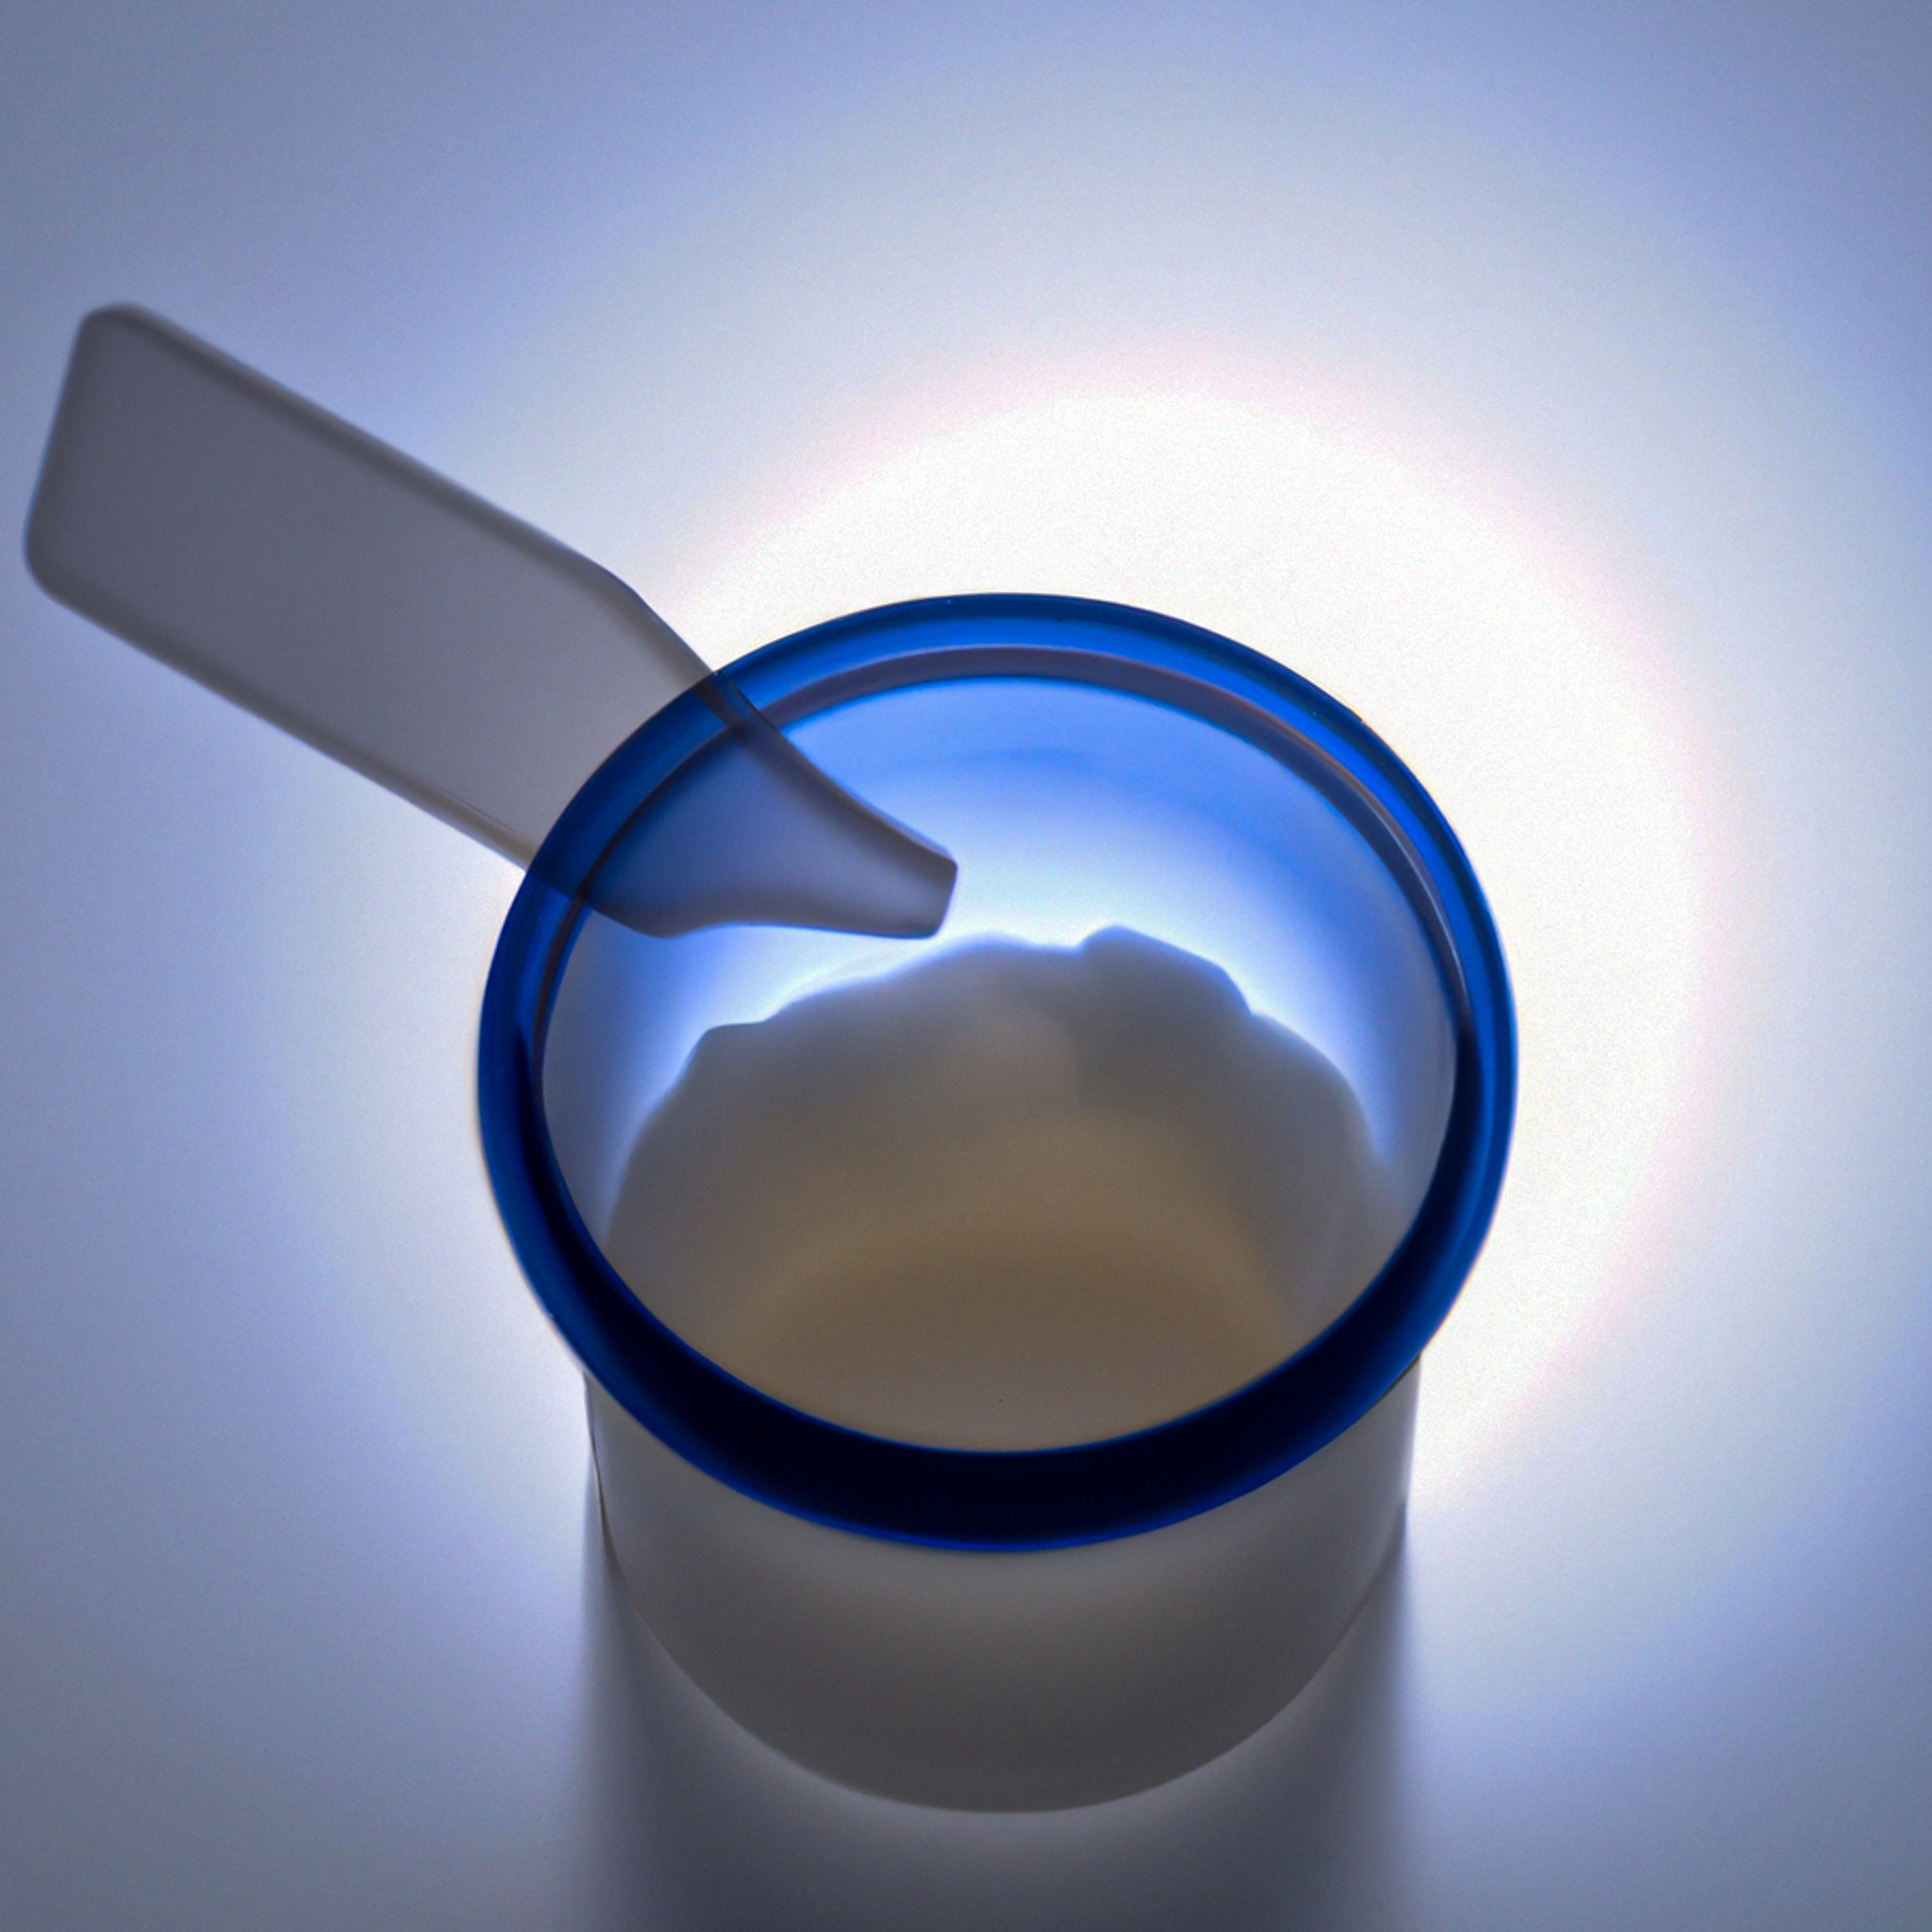

프로포폴 (Propofol)에 대해 간략하게 이야기해보도록 하겠습니다. 포폴(Pofol), 디프리반(Diprivan)이라고도 불리우는 프로포폴 (Propofol)은 대표적인 정맥 마취제에요. 일반인이 접할 수 있는 곳이라면 수면 내시경, 성형수술 등을 진행할 때 정도 되겠네요. 케타민, 미다졸람과 함께 3대 수면마취제로 일컬어지는데요, 부작용이 심한 케타민은 흔히 사용되지 않고, 미다졸람의 경우 전신마취 효과가 제일 좋지만 부작용이 심한 것이 단점이지만 프로포폴의 호흡기 억제로 인한 사건사고로 인해 가장 많이 사용되는 전신마취제라고 할 수 있습니다. 프로포폴이라는 의약품 단어를 우리들이 쉽게 알고있는 이유는 프로포폴 오남용으로 인한 사건사고가 굉장히 많이 발생하기 때문인데요, 대표적인 예로 마이클 잭슨의 사망 원인이 프로포폴 과다 복용이라고 꼽히며 국내에서도 다수의 유명인들의 프로포폴 오남용으로 이름을 올리곤 합니다.

프로포폴은 중환자실에서 마취 유도 및 유지, 시술 진정 등에 사용되는 단기 작용 정맥 진정제-최면제를 이야기해요. 흔히 수면마취제라고 이야기하지만 보다 정확히 이야기하면 수면을 유도해 마취하는 것이 아니라 잠시 뇌가 잠에 들었다고 착각하게 만드는 약물이라고 볼 수 있어요. 프로포폴은 특정 뇌 세포의 활동을 억제하는 신경 전달 물질인 감마-아미노부티르산(GABA)의 활동을 강화하여 진정 작용과 기억 상실을 유발하는거에요. 프로포폴은 일반적으로 훈련된 의료진이 투여해야해요, 호흡 억제 등의 부작용이 있어 조심스럽게 다뤄야하거든요.

프로포폴은 일반인이 제조 및 관리, 사용할 수 없는 약물이구요, 필히 자격을 갖춘 의료 전문가, 일반적으로 마취 전문의가 투여해야 하는 약이에요. 프로포폴은 보통 정맥 주사(IV) 주입을 통해 투여하구요. 투여량과 투여 속도는 개인의 나이, 체중, 의학적 상태, 수행되는 절차 유형을 포함한 여러 요인에 따라 달라지겠지요. 이 부분에 대해서는 특별히 할 이야기가 없을 듯 싶습니다. 일반인이 알 필요도 없고 알 이유도 없으니까요.